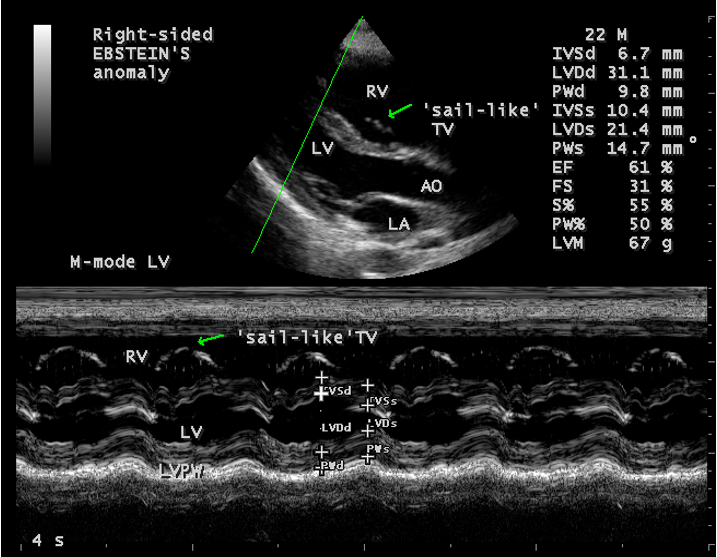

A 22-year old acyanotic male was presented with features of right heart failure and a grade 3/6 systolic murmur at lower left sternal border. 2D echocardiography revealed a normally attached septal tricuspid leaflet (STL), but tethered to the ventricular wall suggesting an Ebstein’s anomaly with severe tricuspid regurgitation swirling around the lateral wall of right atrium and interatrial septum, and a dilated atrium and atrialized RV (right ventricle) as shown in Figures 4 to 8.

Echocardiographic features Echocardiography is the diagnostic test of choice for Ebstein’s anomaly and the first echocardiographic diagnosis was reported by Lundstrom in 1969. The first diagnostic criteria for Ebstein’s anomaly using a multi-crystal two-dimensional system was defined by Hagan in 1974 [33] and they were able to recognize the apical displacement of the septal tricuspid leaflet and an elongated anterior tricuspid leaflet with increased excursion. The septal leaflet of the tricuspid valve attaches chiefly to the ventricular septum , but part of its basal attachment is to the posterior wall of the right ventricle [34] and it normally exhibits a slight but distinct apical displacement of its basal attachment to the central fibrous body compared to the mitral valve. The distal displacement of septal origin of tricuspid valve seems to be the best echocardiographic criterion as the characteristic sign for Ebstein’s anomaly and the degree of maximal displacement in normal hearts varies considerably with a mean difference of approximately 6 mm with mitral valve. To define the anatomic severity of Ebstein’s anomaly, four-chamber view is the best to demonstrate the apical displacement of septal tricuspid leaflet [35]. The ratio between the mitral-to-apex distance and the tricuspid-to-apex distance varies from 1 to 1.2 in normal subjects and 1.8 to 3.2 in patients and it is 3.6 as in Figure 18 with Ebstein’s anomaly. The true distance in the level of insertion of atrioventricular valves is obtained by substracting the tricuspid-to-apex distance from the mitral-to-apex distance with a mean value of 27.25 ± 12 mm in patients with proven Ebstein’s anomaly and it is 60 mm as shown in Figure 18 compared to reference group (5.7 ± 2 mm). Kambe and coworkers calculated the distance between both atrioventricular valves directly as a mean value of 21 mm with a range of 14 to 32 mm [36]. A maximum difference in the level of valve insertion of >15 mm in children and >20 mm in adults is discriminated between normal and Ebstein’s anomaly [37],[38]. Despite this fact, a patient with an ‘unequivocal’ Ebstein’s malformation can be encountered in whom the diagnosis cannot be made with certainity solely on the basis of apical displacement of the septal tricuspid valve leaflet. Occasionally, the leaflet attaches to the trabecular part rather than the inlet part of the septum, the conventional four-chamber view will not reveal any septal insertion as shown in Figures 28 and 29.

The anterior tricuspid leaflet is not involved in the process of downward displacement, it may be abnormally inserted occasionally and Shiina, et al documented the apical displacement of anterior tricuspid leaflet in 14% of cases echocardiographically [39]. The anterior leaflet forms a large, sail-like intracavitary curtain as in Figures 14, 25 and contains muscular strands instead of consisting entirely of a fibrous membrane as in the normal tricuspid valve [40]. It is potentially mobile with a brisk sail-like movement as shown in Figure 21 to 24 [41], free bloating with a ‘whipping motion’ across the right ventricular outflow tract (RVOT) as shown in Figure 26 and in some cases, the movement is restricted due to its adherence to the ventricular wall as in Figure 1 and 2, 4 and 9. It is often fenestrated, may in part be musculaized , inserting into the trabeculations of the right ventricle (RV) as in Figure 28 and rarely, the anterior leaflet forms an ‘atretic’ membrane that spans the midportion of the right ventricular cavity as in Figure 16.